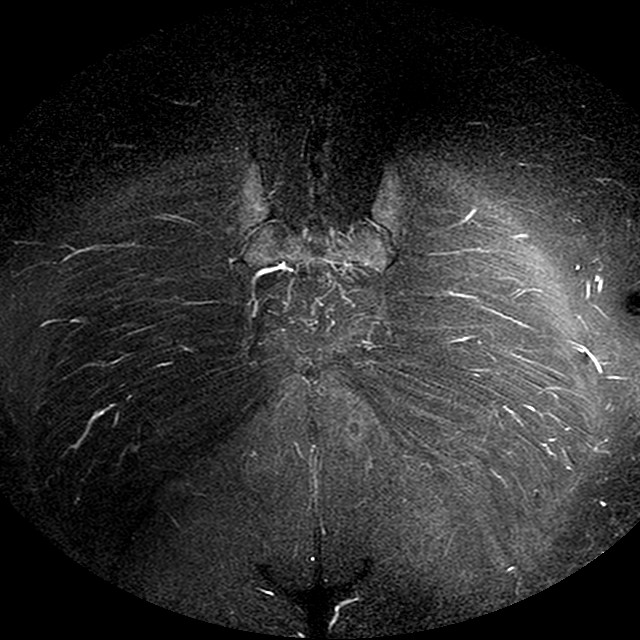

STIR

Evidenti e simmetriche alterazioni osteofitosiche in regione coxo femorale con riduzione delle rime articolari. Degenerazione completa del cercine glenoideo. Non attuali segni di versamento articolare. Non segni di edema osseo che escludono attuale algodistrofia od osteonecrosi. Lieve e simmetrica riduzione del trofismo della muscolatura glutea.